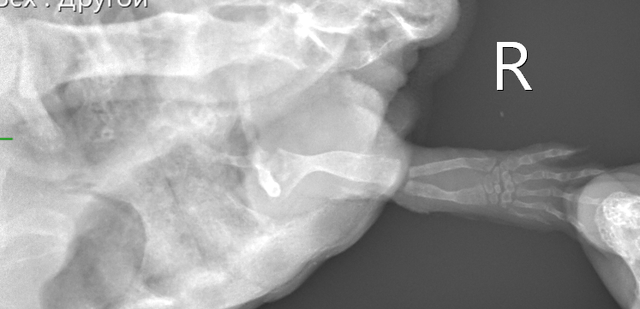

Консультанты moth Ваше имя: Мария Локация: Москва Опубликовано: 7 сентября 2023 Консультанты Опубликовано: 7 сентября 2023 @Алёна.Е. Вам всё в ту же клинику с ней нужно - делать рентген лапы и смотреть что с костями. Если там внутри всё сгнило, то только ампутация. Если нет, то можно пробовать антибиотики. Вы ещё не записывались на приём? Рыбу она поела?

Консультанты moth Ваше имя: Мария Локация: Москва Опубликовано: 8 сентября 2023 Консультанты Опубликовано: 8 сентября 2023 @Алёна.Е. врач ответила, что нужно обязательно рентген. Мускусные черепахи склонны к "гниению" конечностей и скорее всего там гнойный артрит и некроз + сверху бактериальный дерматит. рыбу конечно предлагайте.

Алёна.Е. Ваше имя: Алёна Локация: Пермь Опубликовано: 13 сентября 2023 Автор Опубликовано: 13 сентября 2023 Здравствуйте, были на приёме в клинике 11.09. Рентген сделали, назначили антибиотик, ванны с бетадином и прослушивание. От рыбы также отказывается. Если поможет то лапку попробуем спасти. Фаланги уже рыхлые до локтя. Есть вероятность опухоли, но гисталогию не делали ещё.

Консультанты moth Ваше имя: Мария Локация: Москва Опубликовано: 13 сентября 2023 Консультанты Опубликовано: 13 сентября 2023 @Алёна.Е. а снимков нет на руках? я бы нашему врачу показала, спросить её мнение. Попробуйте предложить улиток, мидий или креветку (желательно сырую) без панциря